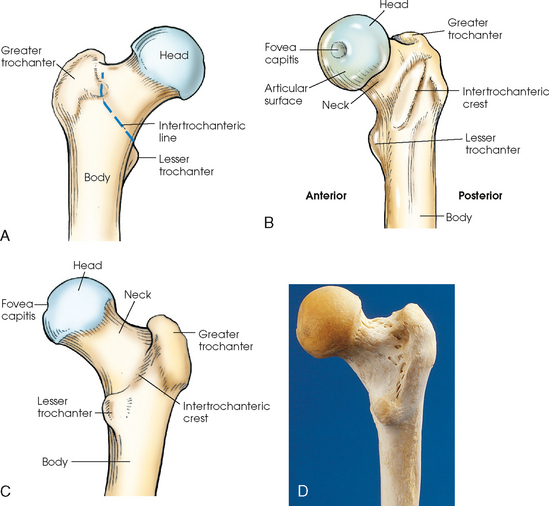

The femur is the longest, strongest, and heaviest bone in the body. The proximal end of the femur consists of a head, a neck, and two large processes: the greater and lesser trochanters (Fig. 7-4). The smooth, rounded head is connected to the femoral body by a pyramid-shaped neck and is received into the acetabular cavity of the hip bone. A small depression at the center of the head, the fovea capitis, attaches to the ligamentum capitis femoris (Fig. 7-5; see Fig. 7-4). The neck is constricted near the head but expands to a broad base at the body of the bone. The neck projects medially, superiorly, and anteriorly from the body. The trochanters are situated at the junction of the body and the base of the neck. The greater trochanter is at the superolateral part of the femoral body, and the lesser trochanter is at the posteromedial part. The prominent ridge extending between the trochanters at the base of the neck on the posterior surface of the body is called the intertrochanteric crest. The less prominent ridge connecting the trochanters anteriorly is called the intertrochanteric line. The femoral neck and the intertrochanteric crest are two common sites of fractures in elderly adults. The superior portion of the greater trochanter projects above the neck and curves slightly posteriorly and medially.

Fig. 7-5 A, Hip joint. Coronal section of proximal femur in acetabulum. B, Axial CT image of hip joint showing acetabulum, head of femur, and superior ramus. C, Coronal CT image of both hip joints. D, Sagittal CT image of the right hip joint. (Modified from Kelley L, Petersen CM: Sectional anatomy for imaging professionals, ed 2, St Louis, 2007, Mosby.)

Table 7-1 and Fig. 7-7 provide a summary of the three joints of the pelvis and upper femora. The articulation between the acetabulum and the head of the femur (the hip joint) is a synovial ball-and-socket joint that permits free movement in all directions. The knee and ankle joints are hinge joints; the wide range of motion of the lower limb depends on the ball-and-socket joint of the hip. Because the knee and ankle joints are hinge joints, medial and lateral rotations of the foot cause rotation of the entire limb, which is centered at the hip joint.